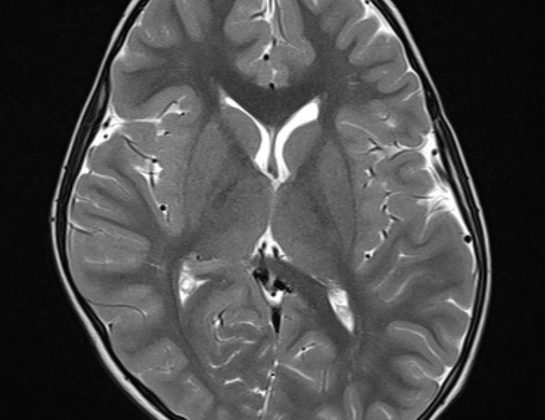

يعاني بعض الأطفال من مشكلة تسطح الرأس، وهو ما يعرف طبيًا باسم Plagiocephaly أو تسطح الجمجمة. هذه المشكلة غالبًا ما تظهر في الأشهر الأولى من حياة الطفل، ويهتم الأهل بفهم تقرير الأشعة لمعرفة مدى تأثير التسطح على شكل الرأس ونمو الدماغ. في هذا المقال سنقدم دليلًا مبسطًا يوضح كيفية قراءة تقرير الأشعة الخاص بتسطح الرأس، وما يجب أن يركز عليه الأهل، دون الدخول في مصطلحات معقدة.

تقرير الأشعة هو ملخص يقدمه الطبيب بعد تصوير الرأس باستخدام تقنيات مثل الأشعة المقطعية أو الرنين المغناطيسي أو التصوير الشعاعي التقليدي. الهدف منه:

الكشف عن أي اختلالات في نمو الدماغ أو العظام.